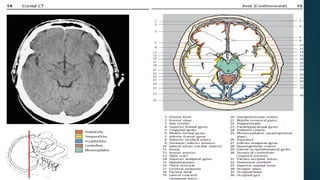

Este documento es el programa para un taller de imágenes del curso de emergencia 2015 impartido por el Dr. Víctor Delgado. El taller se centra en el uso de imágenes médicas para el diagnóstico y tratamiento de pacientes en coma traumático según la base de datos de Marshall. El Dr. Delgado es el único instructor repetido a lo largo del documento.